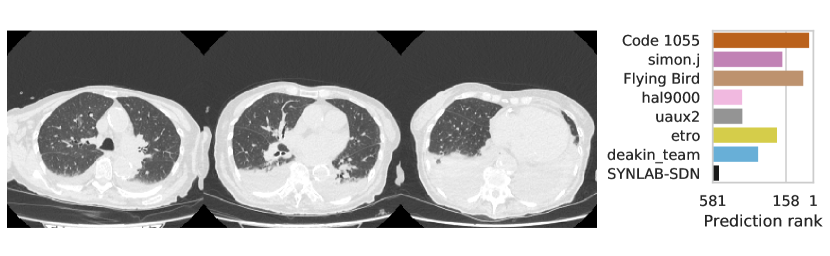

3.2.3 Performance

Table 1 shows the AUC on test set B for COVID-19 presence and severity of the teams that submitted to the Final phase. Figure 4 shows Receiving Operating Characteristics (ROC) curves of the six successful Final phase submissions for discriminating between severe and non-severe COVID-19 subjects from test set B. Figures 5 and 6 show how the finalists ranked the subjects from test set B with severe and non-severe COVID-19 respectively for presence of severe COVID-19. Figures 7 and 8 highlight some individual cases from test set B. During the original STOIC project [67], a logistic regression model was developed to predict severe COVID-19 using clinical variables and CT annotations by radiologists. It was developed and evaluated using the patients from the STOIC who were COVID-19 positive for both RT-PCR and CT, and had unenhanced CT. Of these 4238 patients, 1000 developed severe COVID-19. Revel and colleagues 6 reported an AUC for this model of 0.69 (CI: 0.67-0.71). To compare this model against the results from STOIC2021, an ensemble of the top three solutions for severe COVID-19 prediction was evaluated on the 367 patients from test set B who were COVID-19 positive for both RT-PCR and CT, and had unenhanced CT. 97 of these patients developed severe COVID-19. The top three ensemble achieved an AUC of 0.783 (CI: 0.706-0.848).